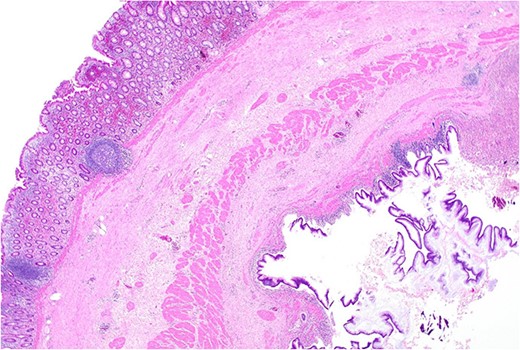

Histopathology macroscopically identified a 42-mm cystic caecal mass adjacent to the ileocaecal valve (Figs 4–5). Microscopic examination revealed a duplication cyst involving the ileal and colonic tissue comprised of a complete duplication of the colonic wall including mucosa, submucosa and muscularis propria, which was shared with the involved colon (Fig. 6). There was no mucosal connection to adjacent normal bowel. There was some ulceration with inflammatory changes in the overlying mucosa suggestive of prior cyst perforation and areas of attenuated villiform mucinous epithelium with features of low grade dysplasia (Figs 7-8). Special stains for organisms (Periodic Acid-Schiff (PAS), Fredericamycin A (FMA), Ziehl-Neelsen (ZN) and modified ZN) were negative. There were no granulomas, heterotopic mucosa or evidence of malignancy. Twenty-nine lymph nodes were identified with no evidence of malignancy.

Area of dysplastic mucosa (right) within the duplication cyst that shares a common wall with the right colon (left), low power.